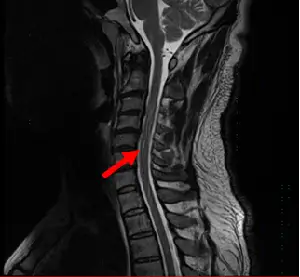

- 影像序列:這是一張頸椎的矢狀面 T2 權重影像(Sagittal T2-weighted MRI)。在此序列中,腦脊髓液(CSF)應呈現高亮訊號(白色),而脊髓(spinal cord)則呈現中等訊號(灰色)。

- 箭號特徵:紅色箭號指向脊髓前方的蜘蛛膜下腔(subarachnoid space)。可以清楚觀察到,原本應該是均勻白色的 CSF 中,出現了不規則、線條狀的低訊號(黑色)陰影。

- 臨床意義:這些不規則的黑色陰影被稱為流動空洞(flow voids),是由於 CSF 的快速或脈動性流動造成的訊號流失。這並非真實的解剖病灶,而是典型的「腦脊髓液流動假影」。